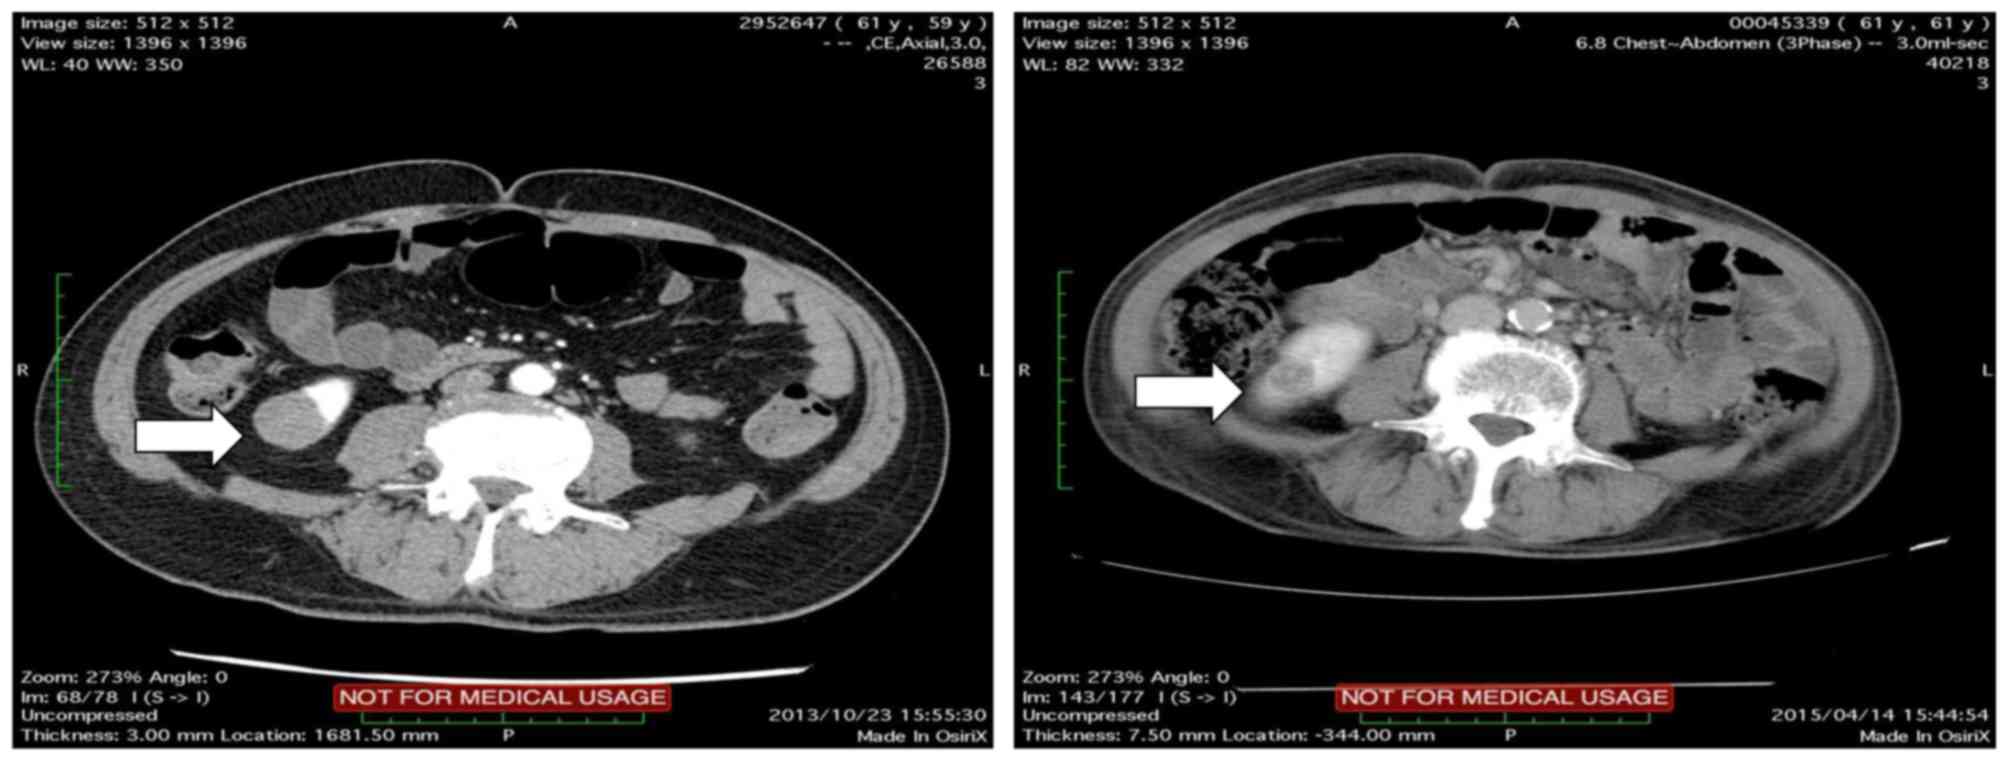

basis. However, due to progression of metastatic bone disease

(Fig. 2), the patient was readmitted

to the hospital. He currently remains alive and is on pazopanib

treatment.